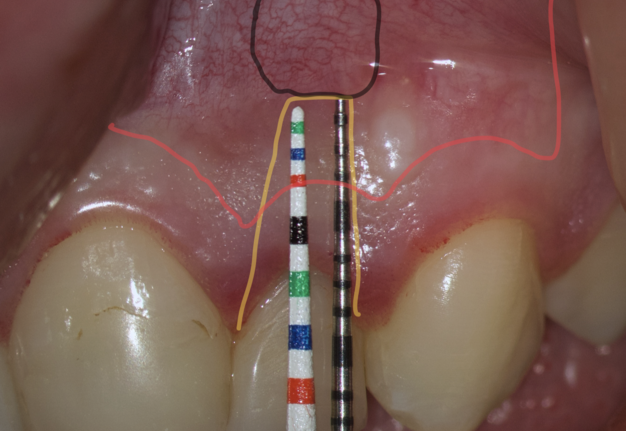

The most popular paramarginal or submarginal flap is the one designed by Clifford Ochsenbein and Raymond G. Luebke (1974) [4, 5]. The Ochsenbein-Luebke flap is formed by a scalloped horizontal sub-marginal incision placed within the attached gingiva, which follows roughly parallel to the contour of the gingival margin. The horizontal incision continues with two vertical releasing incisions [6]. These vertical incisions extend from a point 1 to 2 mm short of entering the mucobuccal fold to a point on the attached gingiva approximately 3 to 5 mm above or below the marginal gingiva and the sulcus depth (Figs 1 and 2) [7, 8].

The submarginal flap is only to be used, when there is a broad zone of attached gingiva with a minimum of 2 mm [9]. The width of the attached gingiva is then calculated on the basis of the distance from the base of the sulcus to the linea girlandiformis (mucogingival junction) [6]. Consequently, the incision must be placed at least 2 mm from the depth of the gingival sulcus. Extensive periodontal probing should be done to establish the depth of the gingival sulcus before the incision is made [10]. Periodontal probing should be conducted not only around the causative tooth but also in the adjacent teeth.

Sometimes the frenulum of the upper lip is massive and for avoid its dissection, it is permissible to perform a submarginal flap with one vertical incision located more distally. It is worth recognizing that this approach is applied to a root with medium length on which microsurgery is performed (Figs 3 and 4).